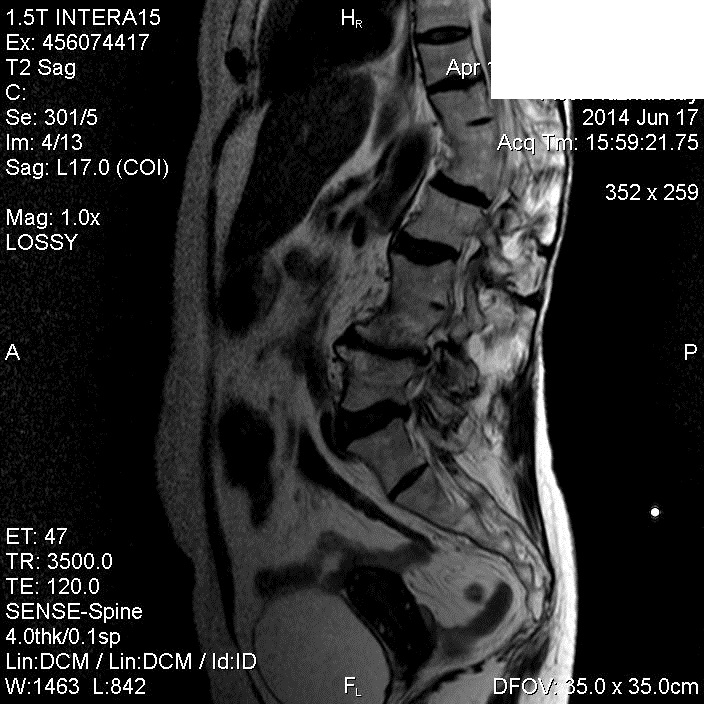

Хороший букет аномалий. Конкресценция, клиновидный (бабочковидный) позвонок, незаращение остистых отростков (spina bifida) ничего не забыл?